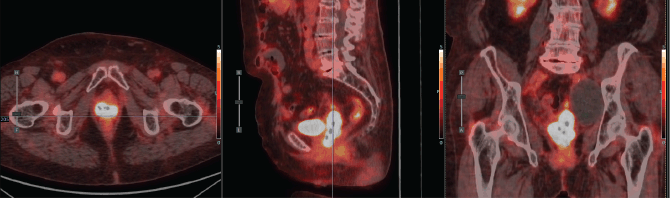

A 75-year-old with a history of hypertension and dilated cardiomyopathy was diagnosed with Stage IIIC2 endometrial adenocarcinoma after hysterectomy, bilateral salpingo-oophorectomy and lymph node dissection revealed one positive para-aortic node. She declined or missed timely adjuvant radiotherapy. Seven months after surgery, the patient presented with a symptomatic recurrence in the vaginal vault and a positron emission tomography - computed tomography (PET-CT) also revealed latero-aortic hypermetabolic adenopathy. She received letrozole for hormone receptor–positive disease and six cycles of palliative chemotherapy with Carboplatin – Paclitaxel, after which she had complete regression of the adenopathy and stability of the disease in the vaginal vault. Then she was treated with palliative EBRT (30 Gy in 10 fractions) to the pelvis and vaginal vault. One year after this treatment, she developed progression of local disease involving the distal vagina and possibly the urethra (Figure 6). The case was discussed in tumour board, and pelvic exenteration was considered but deemed too morbid. She was referred for HDR interstitial BT reirradiation.

Figure 6. Case 2. PET-CT scan prior to BT. Axial, sagittal and coronal section. A hypermetabolic tumour mass in the vaginal vault and a left pelvic lymphocele were observed.